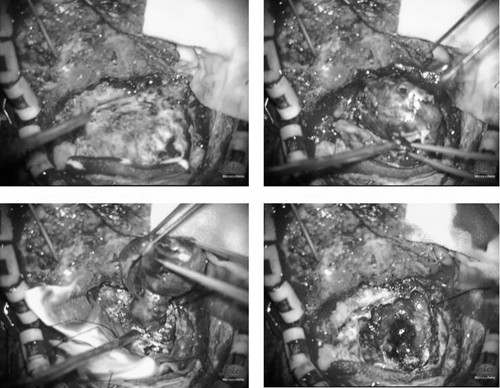

2017-8-14介入栓塞后即行肿瘤切除术

术中肿瘤组织呈红褐色,血供少,肿瘤完整全切除,出血约100ml、未输血。